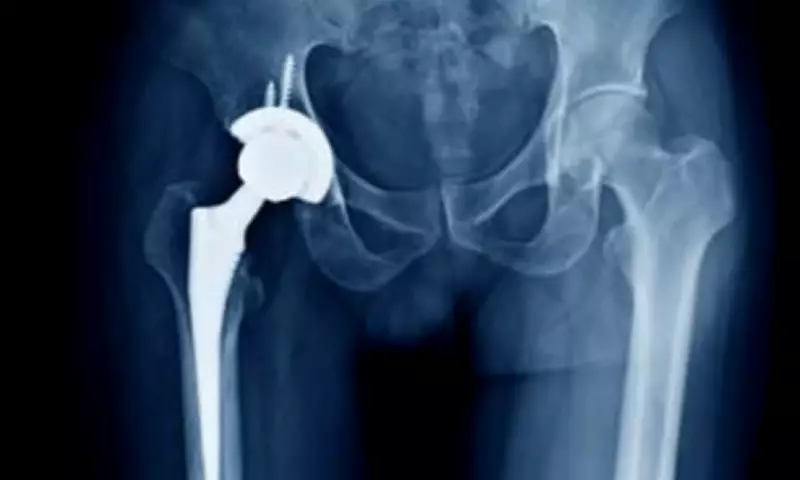

Health leaders have acknowledged that 'competitor cement availability is limited', complicating efforts to address record backlogs exacerbated by pandemic delays and recent funding cuts. Bone cement is utilised in more than 80% of knee replacements and nearly 60% of hip replacements, equating to roughly 15,000 operations monthly across the UK.

Dr Alex Dickinson, Professor of Prosthetics Engineering at the University of Southampton, emphasised the lack of viable alternatives: 'There are other manufacturers of bone cement, but there is not an alternative material that could just be substituted. Implant engineering is a cautious process, and any new technology carries patient risks requiring years of follow-up.'